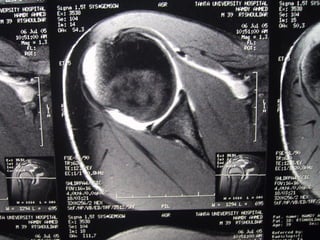

Case 1           Supraspinatus tendinosis

Ab norm   al h igh s ignals e qu al le s s th an flu id